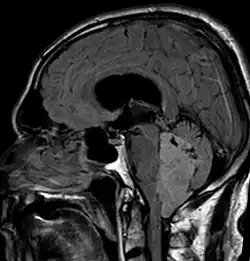

Ependymoma of 4.ventricle in MRI. -

Ependymoma of 4.ventricle in MRI. Left without, right with contrast-enhancement.

An ependymoma is a tumor that arises from the ependyma, a tissue of the central nervous system. Usually, in pediatric cases the location is intracranial, while in adults it is spinal. The common location of intracranial ependymomas is the floor of the fourth ventricle. Rarely, ependymomas can occur in the pelvic cavity.

Ependymomas make up about 5% of adult intracranial gliomas and up to 10% of childhood tumors of the central nervous system (CNS). Their occurrence seems to peak at age 5 years and then again at age 35. They develop from cells that line both the hollow cavities of the brain and the central canal containing the spinal cord, but they usually arise from the floor of the fourth ventricle, situated in the lower back portion of the brain, where they may produce headache, nausea and vomiting by obstructing the flow of cerebrospinal fluid. This obstruction may also cause hydrocephalus. They may also arise in the spinal cord, conus medullaris and supratentorial locations.[7] Other symptoms can include (but are not limited to): loss of appetite, difficulty sleeping, temporary inability to distinguish colors, uncontrollable twitching, seeing vertical or horizontal lines when in bright light, and temporary memory loss. It should be remembered that these symptoms also are prevalent in many other illnesses not associated with ependymoma.

Intracranial ependymomas, including supratentorial and posterior fossa, make up 90% of ependymomas in children. The supratentorial region is the upper brain region, or cerebrum, and contains the lateral and third ventricles. The posterior fossa, or infratentorial, is behind or below this region in the area of the brainstem and cerebellum and contains the fourth ventricle. A majority of intracranial pediatric ependymomas are in the posterior fossa.[15] Patients with intracranial ependymomas typically present with increased intracranial pressure that results in headaches, dizziness, nausea, and vomiting. The third location of ependymomas is within the central canal of the spinal cord. Spinal ependymomas comprise about 65% of adult ependymomas and most often occur in the lumbosacral region.[13] Patients with spinal ependymomas can present with back pain, numbness or weakness in the limbs, and urinary or bowel problems.